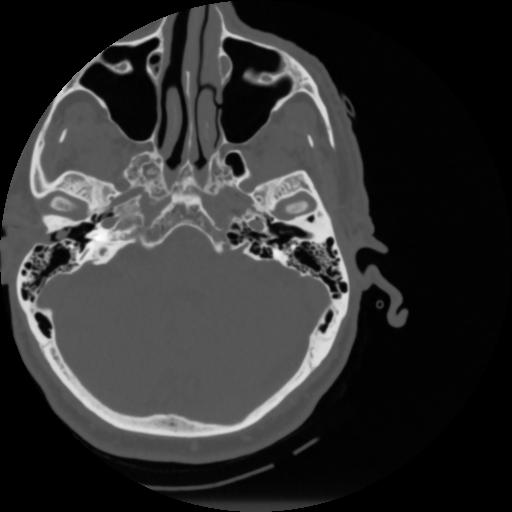

4 CEREBRO,,Vol,0.5,CEREBRO,,